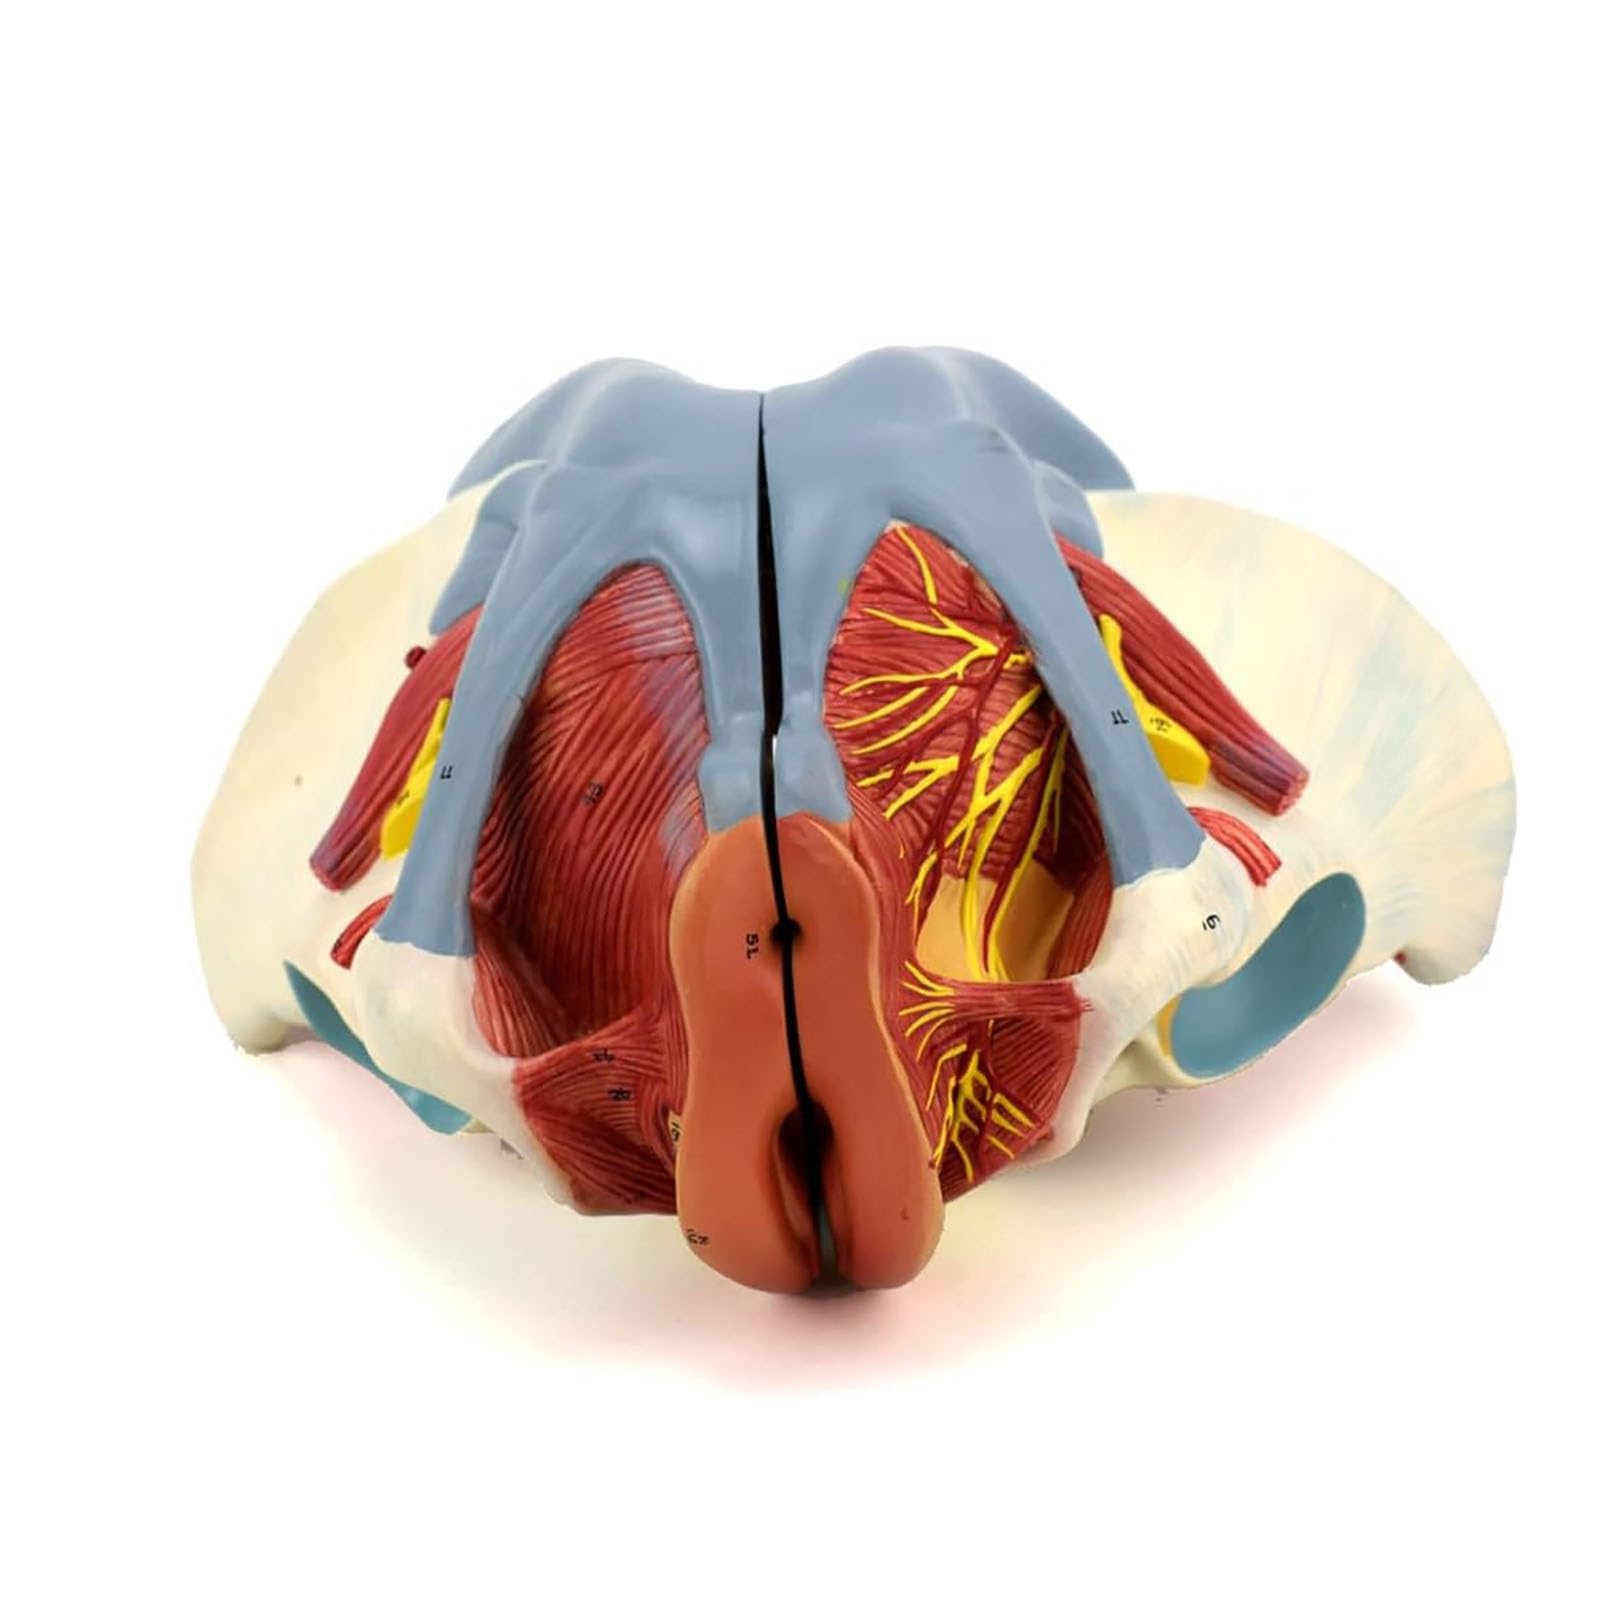

人体模型 骨盤模型 女性 子宮 解剖学的詳細 Amazon | 女性骨盤モデル - 生殖器・血管・神経・筋肉・子宮の詳細なの詳細情報

Amazon | 女性骨盤モデル - 生殖器・血管・神経・筋肉・子宮の詳細な。Amazon.co.jp: 女性 骨盤と 子宮模型 筋肉解剖学 女性骨盤 骨盤底筋と。子宮の解剖模型 - 3480 - GPI Anatomicals - 卵巣の / 実習用 / 女性用。解剖学的詳細を再現した人体模型、頭部と首部が観察可能。- モデル: 人体模型- 部位: 骨盤 大腸 子宮 腹部- 特徴: 解剖学的詳細が再現された構造- 素材: プラスチック製- サイズ: 約30cmの高さご覧いただきありがとうございます。絵画用に模型を購入しましたが使用をしないままでしたのでお譲りします⭐︎とても丁寧な作りでおすすめです◎。h20-1-1280x720.jpg。